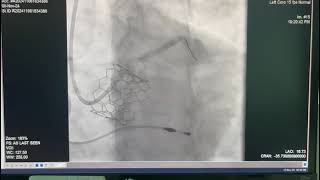

Viveka Kumar (MBBS & MD (Medicine) Is Currently The Principal Director & Chief of Cath Labs (Pan Max) – Cardiac Sciences at Max Hospital, Saket, New Delhi.

An Interventional Cardiologist by profession, Dr Kumar also holds a super speciality degree from GSVM medical college, Kanpur.